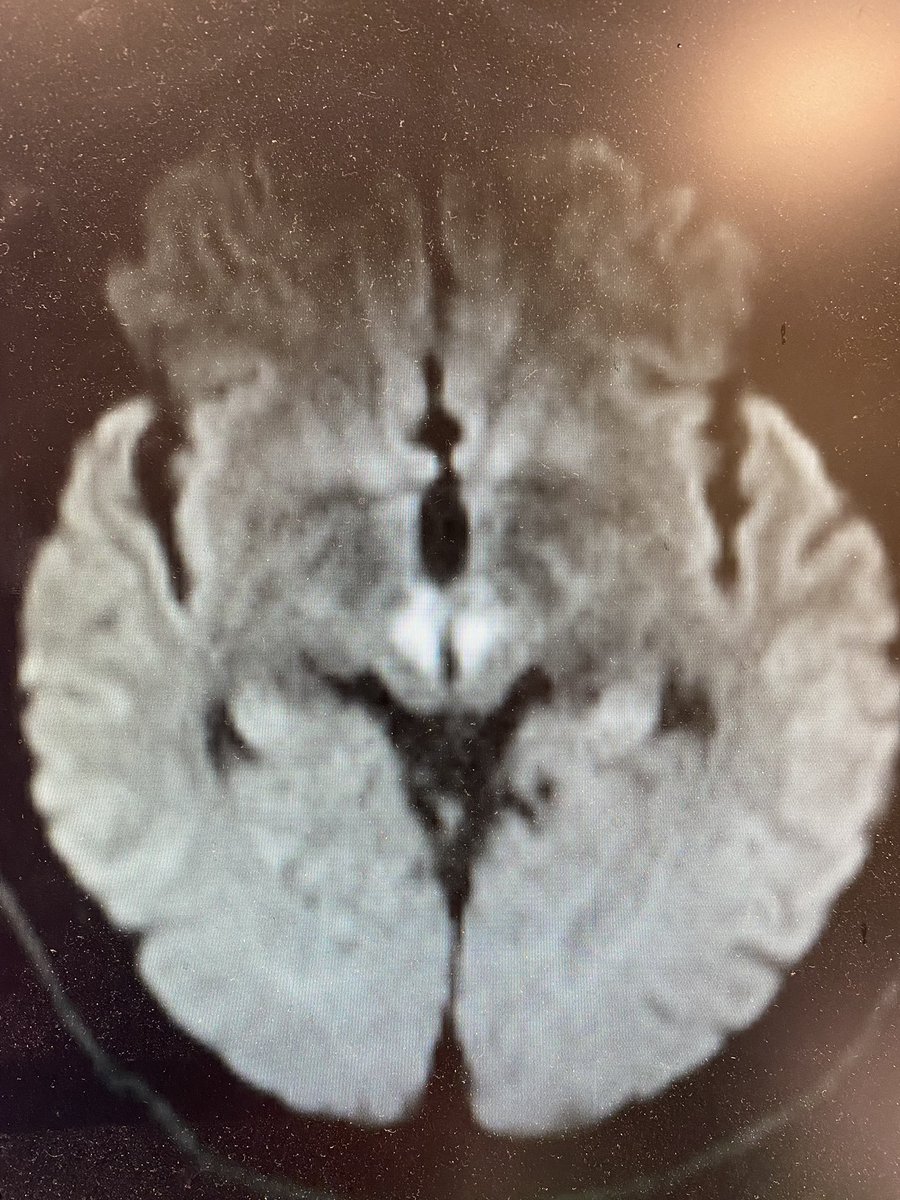

What is your diagnosis now? Only one left is serotonin syndrome which would fit except for the right pupil… Repeat ct now makes diagnosis clearer and mri confirms 5/x

What is your new diagnosis? 6/x

Yup! 7/x

You got it! Artery of Percheron stroke leading to depressed mental status and nuclear IIIrd nerve palsy! Here is a first reference bmcneurol.biomedcentral.com 8/x